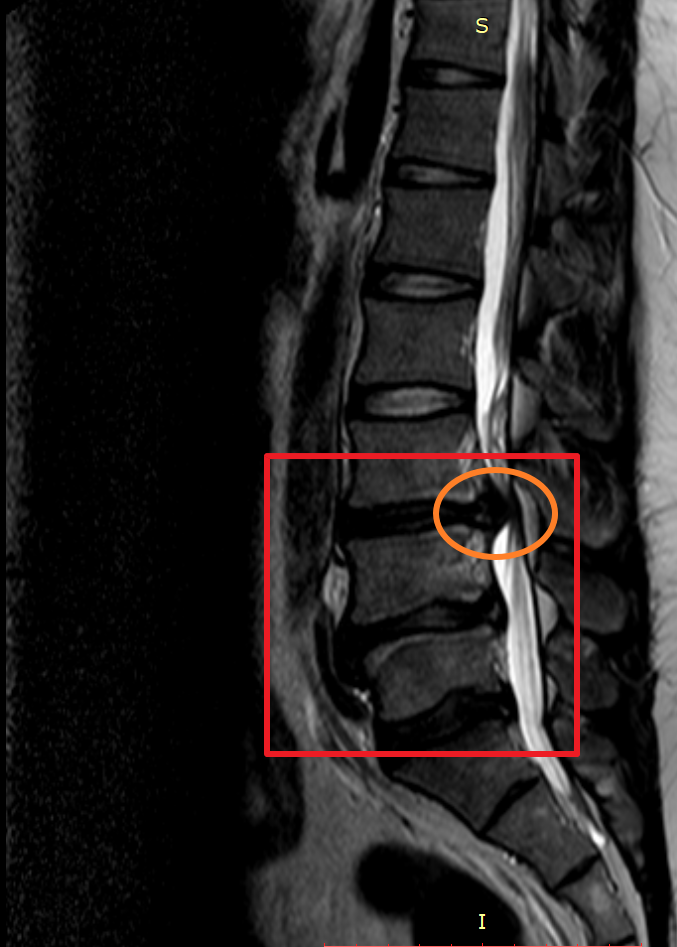

마지막으로 제가 촬영했었던 MRI 촬영 이미지를 첨부해 볼까 합니다. 이미지 순서대로 2014년, 2018년, 2020년 촬영했던 MRI 사진입니다. MRI 촬영 당시 허리디스크 상태가 좋지 않은 상황에서만 세 차례 찍었던 것이기에 이점도 고려해서 참고하시면 좋을 듯합니다.

이미지를 보시면 빨간색 네모 칸에 하얀색 기다란 세로 라인이 신경이 지나가는 부분이며 가장 바깥쪽 두꺼운 흰색 부분은 배 쪽의 지방입니다.

2018년 첫번째 허리 디스크가 첫번째 디스크가 여전히 눌려져 있으며 추가로 두번쨰 디스크가 신경을 많이 누르고 있으며 세번째 디스크는 조금씩 나오는 상황.